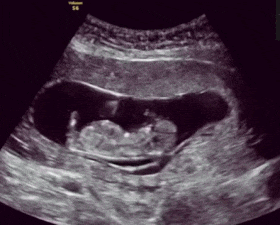

胎动 , 是胎儿在腹中冲击子宫壁的一种动作 , 也是判断胎儿健康与否的一种简单方法 。也就是说 , 我们可以通过胎动的频率、力度及节奏感 , 就能判断出胎儿的健康状况 。

一般而言 , 正常的胎动一小时不少于3-5次 , 12小时的胎动次数总数在30-40次以上为正常 。当然 , 也有些胎儿12小时的胎动能达到百次左右 , 但只要是有节奏、有规律的胎动 , 都是胎动的正常表现 。

正确的数胎动方法应该是按12小时胎动计数 , 即早、中、晚固定时间各测1小时胎动数 , 3次相加总数乘以4 , 即为12小时胎动数 。因为餐后血糖水平较高 , 宝宝也精神饱满 , 拳脚会比较活跃 。

如果12小时胎动数大于30次 , 说明胎儿状况良好 , 如果12小时还不到10次 , 就表明胎儿可能缺氧;若连续12小时没有胎动 , 就应该立即采取抢救措施 。